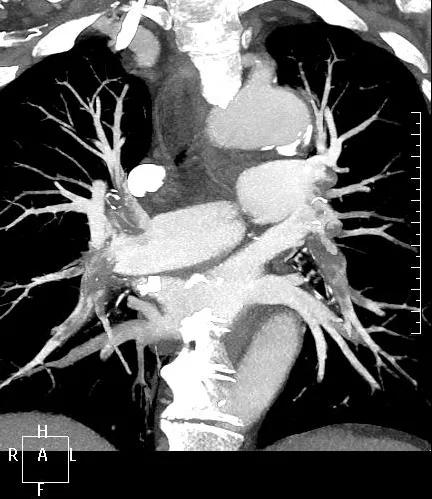

近日,一名港胞翁阿姨在我市突發(fā)急性肺栓塞,生命垂危。市二院在接到120出車指令后,迅速響應(yīng),患者入院后開通綠色通道,經(jīng)急診科、心內(nèi)科、介入科、重癥醫(yī)學(xué)科等多學(xué)科專家開展聯(lián)合會(huì)診,并于當(dāng)晚9點(diǎn)行“下腔靜脈、肺動(dòng)脈造影+導(dǎo)管溶栓+濾器植入術(shù)”,患者終于轉(zhuǎn)危為安,經(jīng)后續(xù)治療與精心護(hù)理,病情逐漸穩(wěn)定,現(xiàn)已轉(zhuǎn)入普通病房。